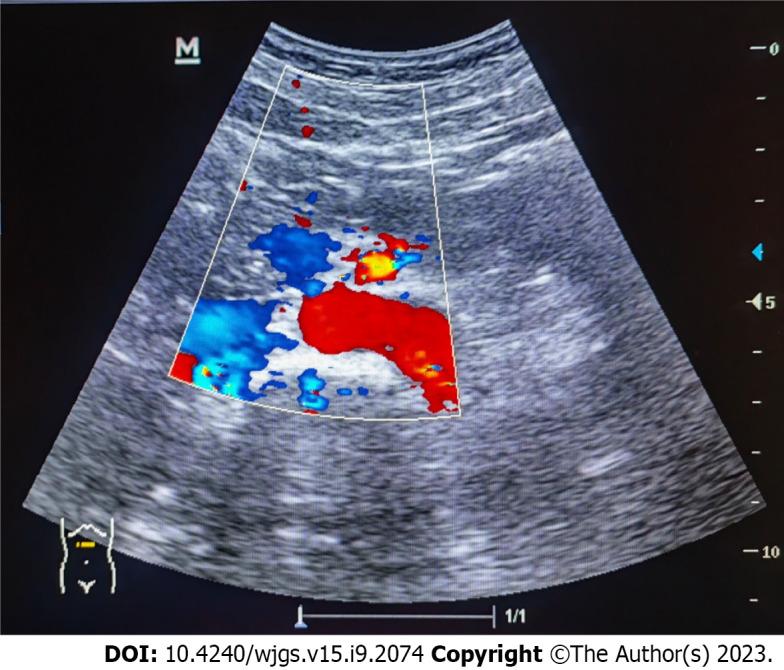

A previously healthy 27-year-old woman presented with abdominal pain following a history of fatigue and consumption of cold water. Laboratory investigations, physical examinations, and enhanced abdominal computed tomography (CT) suggested systemic lupus erythematosus complicated by LMV. She received treatments, such as GI decompression, somatostatin, glucocorticoids, and immunosuppressants, and was evaluated using color ultrasonography. Twenty days later, the patient reported no stomach discomfort and was able to consume semi-liquid food. Laboratory investigations showed that inflammatory factors decreased to normal levels and complement levels increased slightly. One year after discharged, she recovered with methylprednisolone being tapered to 4 mg per day, mycophenolate mofetil to 0.75 g bid, and hydroxychloroquine to 0.2 g bid; however, only C3 complement level was slightly below the normal level.

Early diagnosis of LMV is essential for successful treatment; this depends on a combination of clinical manifestations, laboratory investigations, and imaging findings. Enhanced CT is preferred, but ultrasonography can be used for prompt screening and follow-up.